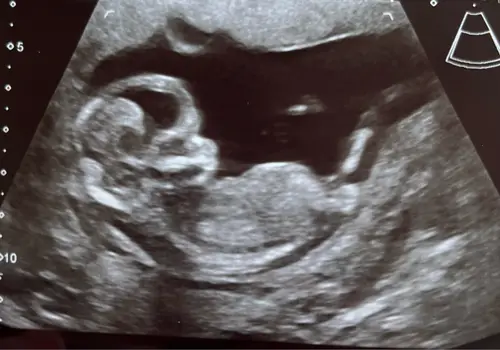

Kan iemand hier iets herkennen? Echo van 13+5

Ik vind ze alle 3 best onduidelijk